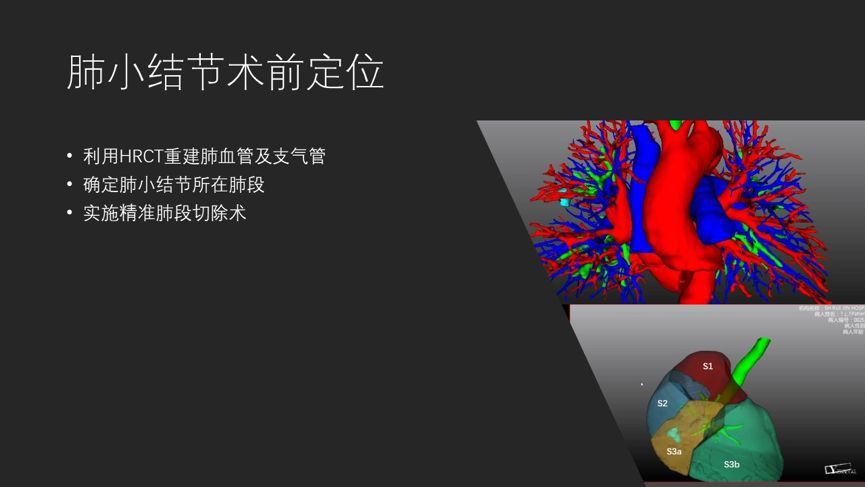

⑤ 可以通过特殊软件重建结节与气管及血管的关系,对结节定位有极高应用价值,是精准解剖性肺段切除术的有力保障。